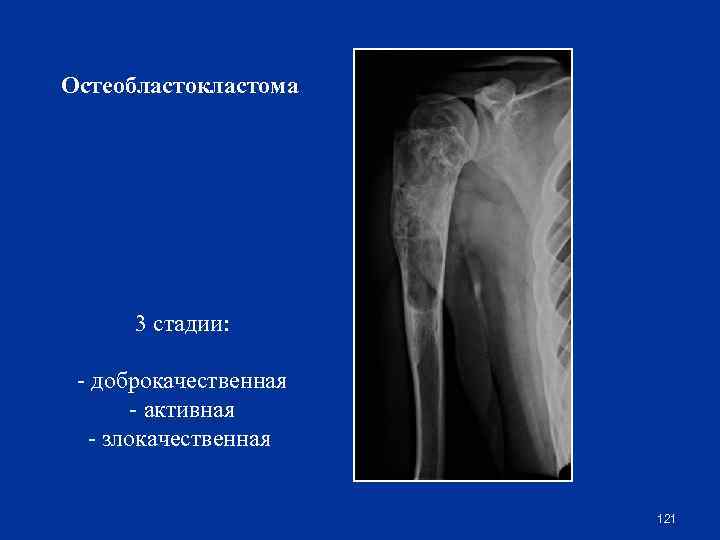

Остеобластокластома 3 стадии: - доброкачественная - активная - злокачественная 121